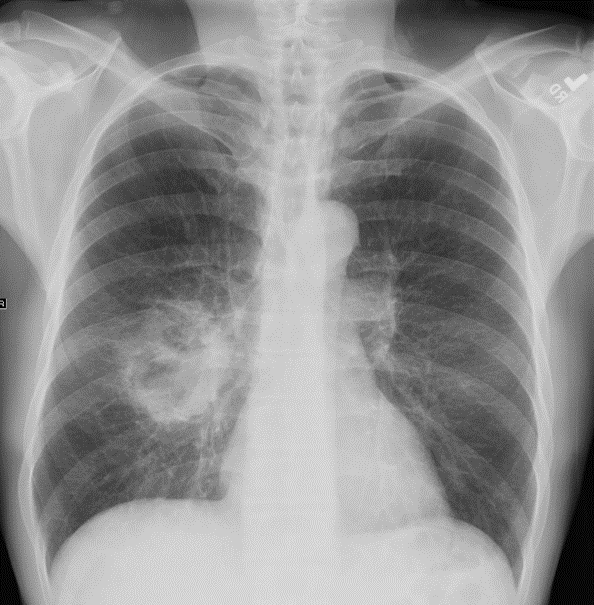

Q

A

• white-greyish mass with black carbon deposits

• SCCs often show soft, friable areas of necrosis and this often causes central cavitation within the tumour